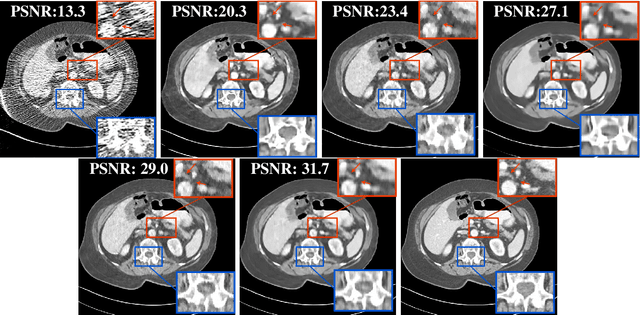

Abstract:Recent years have witnessed growing interest in machine learning-based models and techniques for low-dose X-ray CT (LDCT) imaging tasks. The methods can typically be categorized into supervised learning methods and unsupervised or model-based learning methods. Supervised learning methods have recently shown success in image restoration tasks. However, they often rely on large training sets. Model-based learning methods such as dictionary or transform learning do not require large or paired training sets and often have good generalization properties, since they learn general properties of CT image sets. Recent works have shown the promising reconstruction performance of methods such as PWLS-ULTRA that rely on clustering the underlying (reconstructed) image patches into a learned union of transforms. In this paper, we propose a new Supervised-UnsuPERvised (SUPER) reconstruction framework for LDCT image reconstruction that combines the benefits of supervised learning methods and (unsupervised) transform learning-based methods such as PWLS-ULTRA that involve highly image-adaptive clustering. The SUPER model consists of several layers, each of which includes a deep network learned in a supervised manner and an unsupervised iterative method that involves image-adaptive components. The SUPER reconstruction algorithms are learned in a greedy manner from training data. The proposed SUPER learning methods dramatically outperform both the constituent supervised learning-based networks and iterative algorithms for LDCT, and use much fewer iterations in the iterative reconstruction modules.